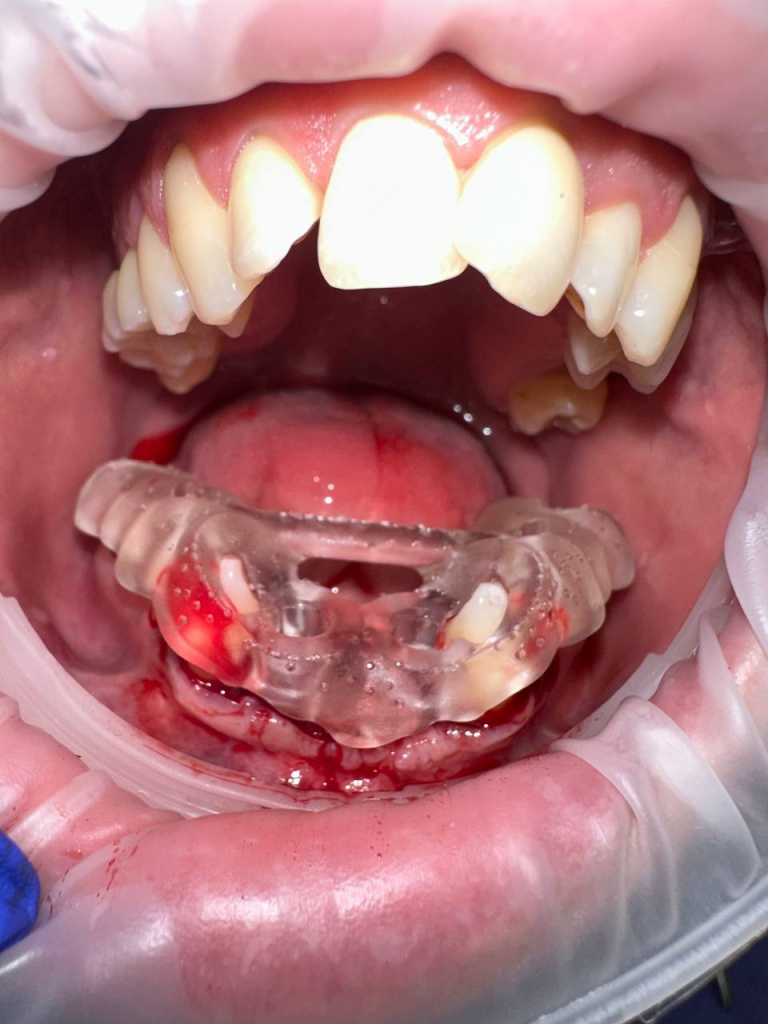

Уже много лет использую в своей практике имплантаты IMPRO. В этот раз мне предоставили линейку IMPRO Respect нового дизайна с широкими лепестками резьбы по отношению к телу имплантата. За счет чего получилось установить имплантаты в переднем отделе в узком гребне и с плохим костным предложением пациента. Ни разу не сталкивалась с осложнениями или проблем с имплантатми IMPRO Implantem. В этот раз не было исключением, была проведена операция через навигационный шаблон, имплантаты стабилизировались с хорошим торком. Хирургический набор и протоколы достаточно просты и удобны. Будем ждать ортопедической части, спустя месяц имплантаты стоят хорошо!

Пациент — мужчина 54 года.